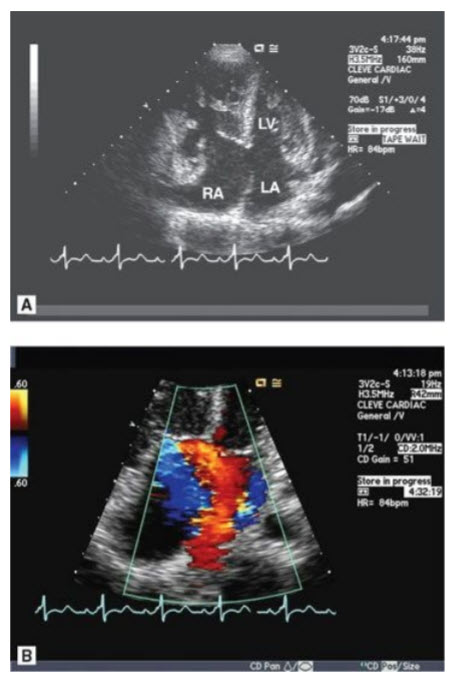

A 36-year-old man with a history of hypertension on medications for 5 years presents to your office with complaints of dyspnea on exertion and is found by his internist to have a heart murmur. Below are some representative views from his TTE (Figs. below A–E).

A. Suprasternal notch view in 2D (TTE). B. Suprasternal notch with color Doppler. C. Continuous-wave Doppler in the descending aorta from the suprasternal notch. D. Parasternal long-axis view in systole. E. Parasternal long-axis view with color Doppler.

What is the diagnosis?

Coarctation of the aorta with bicuspid AV with AI. The patient is a young man with hypertension beginning in his late 20s or early 30s. Secondary hypertension must be considered and ruled out in this patient. When he was initially diagnosed he should have had his blood pressure checked in both arms and legs in consideration of a coarctation of the aorta. Note: Someone may also notice rib notching on a chest X-ray. Other etiologies that should have been excluded include renal artery stenosis (more commonly seen in women if caused by fibromuscular dysplasia), pheochromocytoma, Cushing syndrome, or primary aldosteronism. This patient’s heart murmur was a diastolic murmur from AI caused by prolapse of a bicuspid AV. At least 50% of patients with a coarctation have a bicuspid AV. Fewer patients with bicuspid AV have a coarctation. Note that bicuspid AVs dome (doming aortic leaflets are seen in Fig. D in question) and could be mistaken on initial glance in long axis with a rheumatic AV. However, in addition to doming there is prolapse of the conjoined cusp (which would not be seen in a rheumatic valve) and the anatomic situation could be clarified with a good short-axis view.